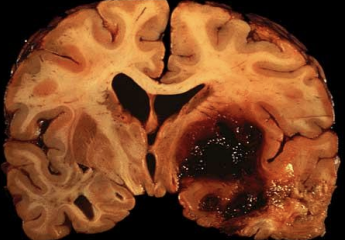

Intracerebral Hemorrhage

Hemorrhage into the brain and brainstem (bleeding in brain tissues).

Most common sites are the thalamus and basal ganglia

Also possible: Brainstem (especially pons) and cerebellum

May be caused by aneurysm: pouch formed in weakened arterial walls

If aneurysm in cerebral artery bursts, severe aphasia is likely (big accumulation big burst)

Hemorrhage into the brain and

brainstem (bleeding in brain tissues).

Most common sites are the

thalamus and basal ganglia

May be caused by aneurysm: pouch formed in weakened

arterial walls

If aneurysm in cerebral artery bursts, severe aphasia is likely